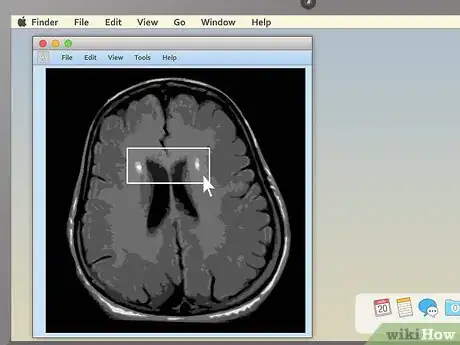

3Use cross-sectional views to spot abnormalities in brain MRIs. MRIs of the brain tissue are often used to check for brain tumors, abscesses, and other serious problems that can affect the brain. The easiest way to see these things is usually to choose the cross-sectional view, then descend slowly from the top of the head downward. You're looking for anything that's not symmetrical — a dark or light patch that's on one side but not the other is cause for concern.

- Brain tumors often take the form of round, golf ball-like growths in the brain which will usually show up as either bright white or dull grey surrounded by a ring of white. However, other brain problems (like multiple scleroses) can also have a whitish appearance, so this alone may not be a sign of a brain tumor.